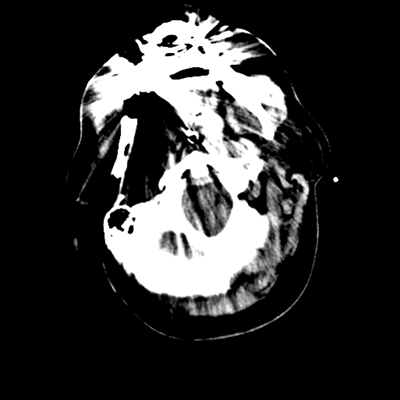

CTP

Starting with the non-contrast head CT, we can appreciate that there's actually not much residual subarachnoid blood at all; it's essentially all resorbed already (and cleared through the EVD). The ventricular caliber is stable. With the CTA head (for convenience's sake, the MIPs were shown), it's subtle, but we can see that the PCAs on each side are not as smooth and regular. The right MCA, starting at the bifurcation, also becomes narrower. This is [radiographic] vasospasm. Now, looking at the CT perfusion-- specifically, the Tmax (MTT) map that were selected-- there's clearly some abnormality within the bilateral cerebellar hemispheres and occipital lobes. Not a lot, but it's there. Delving further into this map, we can appreciate that the areas of abnormality are mainly green, signifying that these areas have Tmax > 6 seconds. This is the threshold that is specific, not sensitive, for vasospasm.

Putting this all together, we have thus identified radiographic vasospasm with the vessel imaging, with perfusion abnormalities that are concordant with it. Does the area of vasospasm and hypoperfusion correlate with the patient's clinical exam?

Yes! It does. The patient had a decline in level of consciousness with diffuse loss of motor function. This does correlate to the basilar territory. (Alternatively, bilateral MCA vasospasm could also be responsible, reminding us that a decline in consciousness could technically be focal/multifocal.) Thus, we can say that this patient does have clinical vasospasm. Whether this will develop into irreversible DCI remains to be seen; at least, the non-contrast head CT and the other portions of the CT perfusion (not shown) currently don't [yet] suggest infarction.